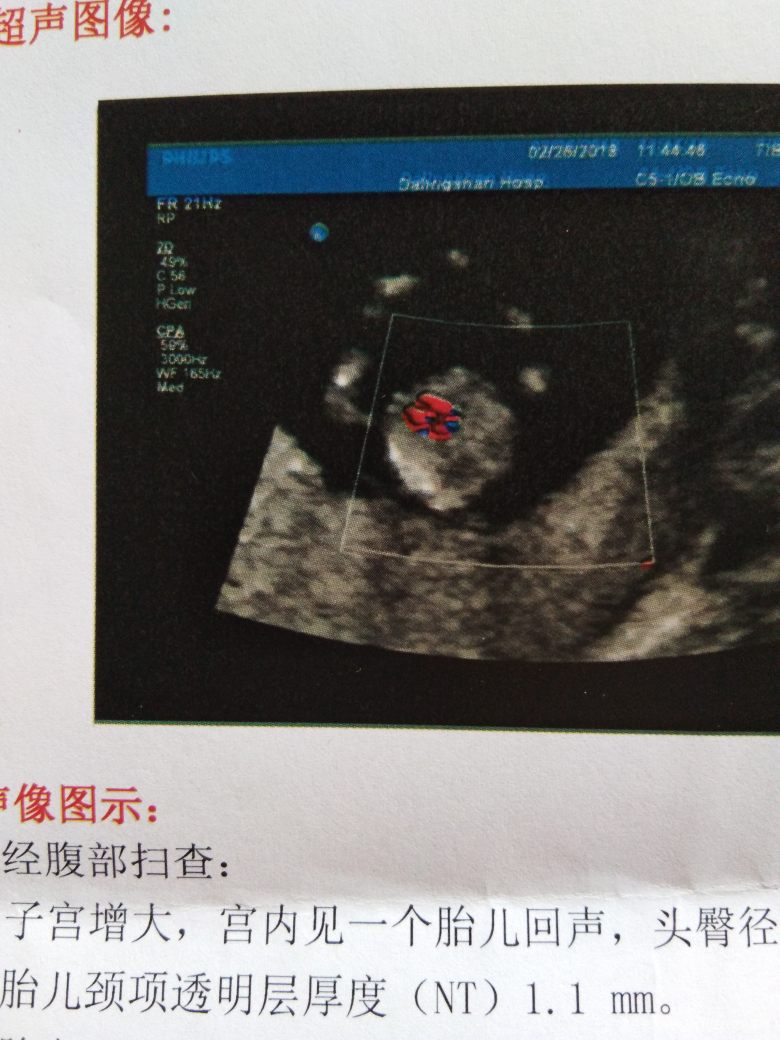

今天上午检查的结果!请帮忙看下